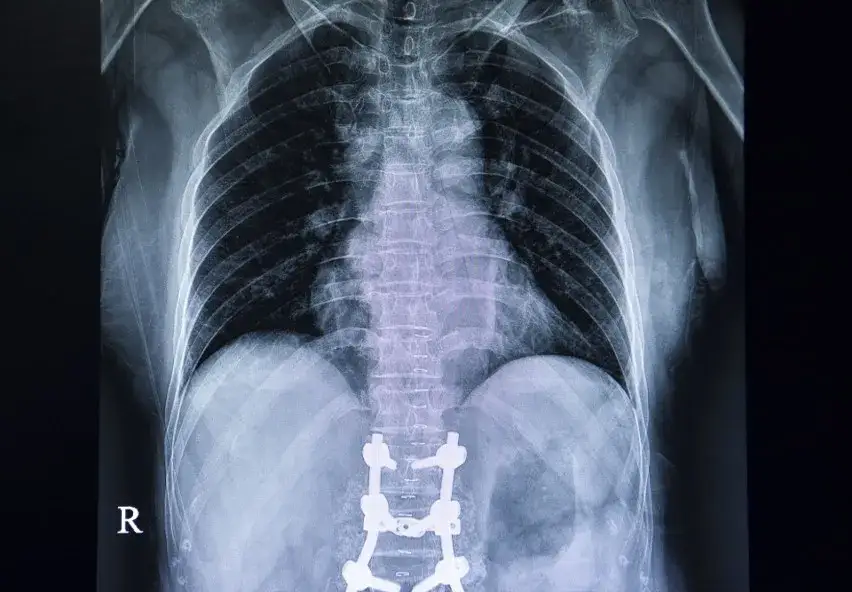

- Ewentualnie: wcześniejsza dokumentacja medyczna (np. wypisy ze szpitala, wyniki badań obrazowych RTG, USG, rezonans magnetyczny, tomografia komputerowa), która może być pomocna dla fizjoterapeuty lub lekarza rehabilitacji w ocenie Twojego stanu.